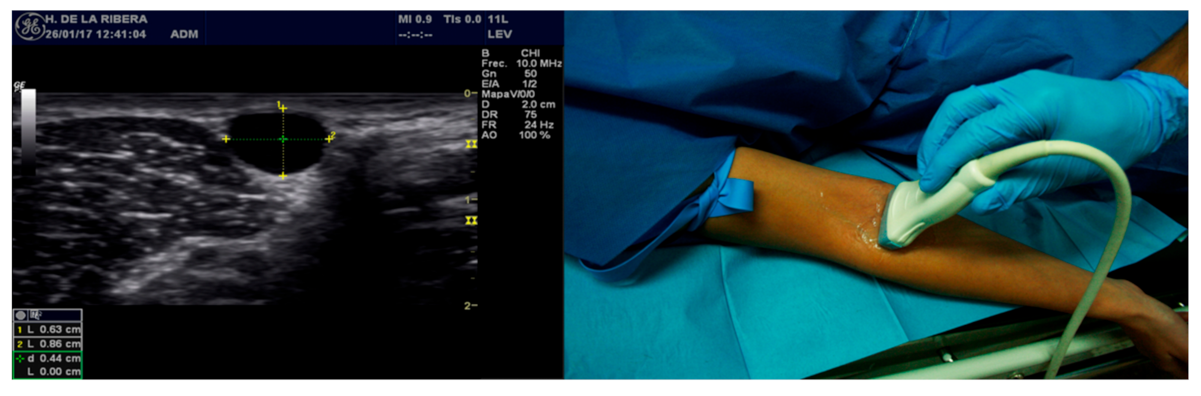

Moreover, in the cases group, a study was conducted in which the following descriptive objectives were analyzed: to evaluate the existence of a relationship between the depth of the vessel and the complications, and to determine if the gauge of the catheter could be determined according to the diameter of the vessel cannulated. To avoid biases, only a transversal plane or short axis was utilized (Figure 1). This plane was selected as opposed to the longitudinal one in order to obtain references of the structures adjacent to the vessel selected, as well as to be able to correct the trajectory of the needle through the use of the “ring down” method. This plane requires the use of the triangulation measurement principle. As the trajectory of the needle could not be visualized, as in the longitudinal plane, the puncture site must be calculated on the basis of the Pythagorean Theorem: using an angle of entry of 45°, the distance to the transductor will be approximately the same as the depth in which the center of the vein is found. The differentiation between the venal and arterial vessels was conducted through the compression technique, and if doubt arose, a Pulsed-Wave Doppler was utilized.

Figure 1.

Measurement of the vein through a transverse plane. Source: author created.

As shown in Figure 2, the following equipment was utilized: the ultrasound machine from emergency services, a LOGIQ P5 750VA from General Electric Healthcare with an 11 mHz linear probe. Peripheral venous catheters model InsyteTM AutoguardTM with gauges (G) ranging from 14G to 26G, with the following measurements: 26G 0.62 × 19 mm; 24G 0.7 × 19 mm; 22G 0.9 × 25 mm; 20G 1.1 × 30 mm; 18G 1.3 × 48 mm. Aside from the above, the following equipment for cannulation was used: compressor; non-sterile gloves; antiseptic solution: 70% alcohol, chlorhexidine alcohol 2%; gauze; three-way valve or extension; 10 mL syringe; 10 mL saline solution; dressing for setting the line; conducting gel if an ultrasound was performed; and extraction hood, fitting, and analytical extraction tubes, if needed.

Figure 2.

Equipment needed for ultrasound-guided peripheral venous cannulation. Source: created by author.